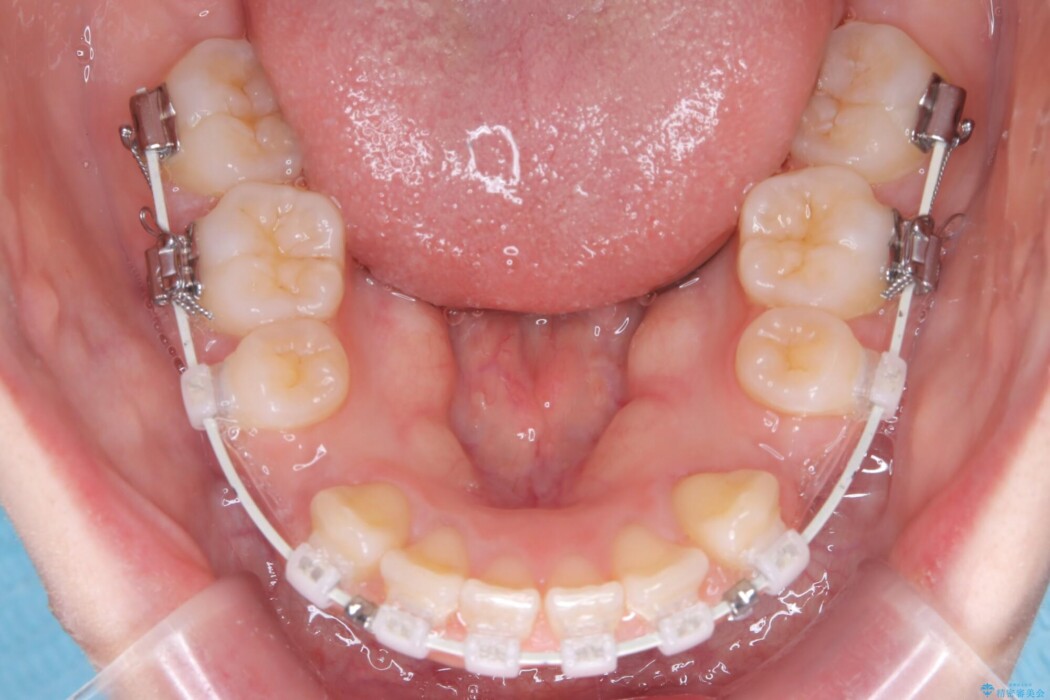

矯正検査の結果、前歯が外側に強く倒れ込んでいる「唇側傾斜(しんそくけいしゃ)」が認められ、口元の突出感の原因になっていました。

この傾斜を根本から正し、前歯を十分に後方へ下げるスペースを確保するため、上下左右の4番を抜歯し、目立ちにくい審美ワイヤー装置にて治療を行うこととしました。